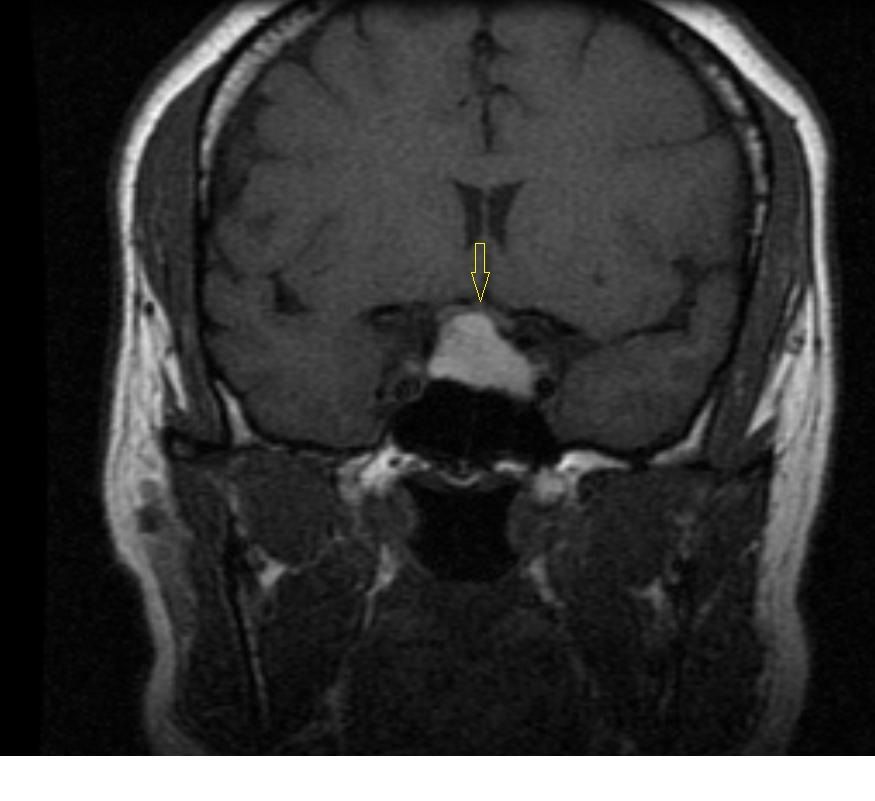

Figure A1. Coronal T1-weighted image showing hyperintense pituitary macroadema, 2.2 x 1.8 x 1.5 cm (arrow), consistent with hemorrhagic pituitary macroadema. Note extension into left cavernous sinus abutting on left internal carotid artery and deforming optic chiasm.

The initial brain scans were obtained 6 months after her initial diagnosis (3 months into her pregnancy) and revealed a hemorrhagic pituitary macroadenoma (Figures A1-4). The patient recollects that a week before the scan, she suffered an episode of severe headache with visual disturbance of the right eye. She did not seek medical attention at the time but did keep an appointment for the brain imaging the following week. At the time of the imaging, she reported that her symptoms had fully resolved.